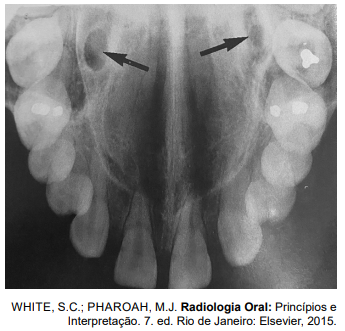

Analise a imagem radiográfica a seguir.

As estruturas anatômicas apontada pelas setas pretas correspondem ao

As estruturas anatômicas apontadas pelas setas pretas correspondem aos